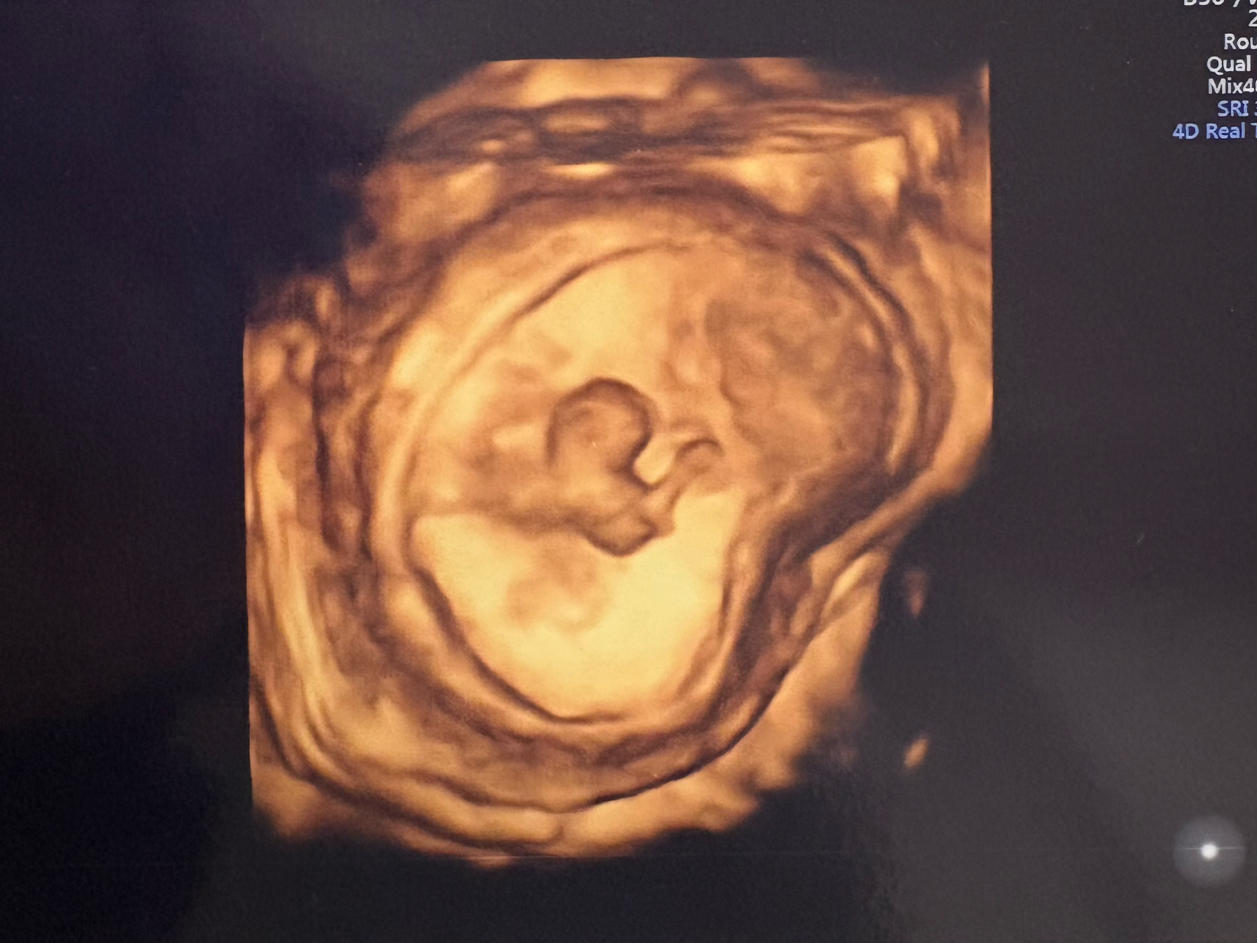

나만 이런 걸까. 임산부 커뮤니티에선 비슷한 주수의 사람들이 초음파 사진을 자랑하고 있었다. 새까맣고 흐릿한 사진을 보고 ‘귀엽지 않나요?', '드디어 젤리곰이 됐어요!'라며 감탄하는데 난 아무 감흥이 없었다. 내눈에 아기집은 블랙홀, 아기는 강낭콩 같았다. 신기하긴 해도 귀엽다는 말은 안 나왔다. 또 나는 입덧 수액 효과 / 임산부 편한 속옷 등 철저히 나를 위한 정보만 찾고 있는데 누구는 참치캔을 먹으면 아기에게 해로운지, 누구는 태아보험을 뭘로 가입해야 하는지 궁금해했다. 밤마다 태담을 한다는 사람도 있었다. 반면 나는 배에다 이름을 부르거나 말을 거는 게 낯간지러웠다. 평소엔 mbti 대문자 F(감정형)면서 이 문제에서만큼은 지독한 T(사고형)가 된 것 같았다.

나를 빨아들일 블랙홀

그리고 강낭콩

그 사이 강낭콩이었던 아기는 머리와 팔다리가 생겨 제법 인간의 형태가 되었고 그제야 초음파 사진을 몇 번이고 들여보게 됐다. 심장 소리는 들을 때마다 적응이 안 되고 아무래도 주작 같았지만(?) 쪼끄만 게 열심히 숨을 쉰다니 꽤 깜찍하고 소중했다.